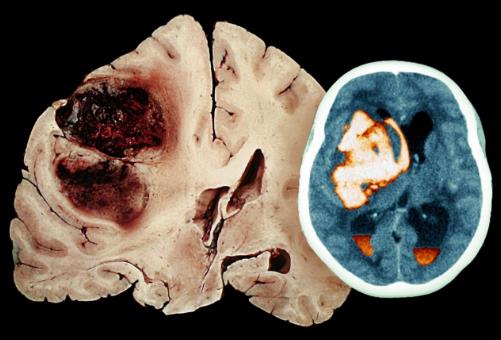

在了解脑出血的前兆之前我们先要看看什么是脑出血。脑溢血又称脑出血、发病急且进展迅速。数据显示在发生脑出血的患者中50%有先兆症状。脑溢血是指脑内微血管破裂出血是老年人的常见病好发于寒冷的冬季。常常表现为突然的一侧肢体麻木、无力或瘫痪,因此病人会在毫无防备的情况下跌倒或手中的物品突然掉地同时伴有口角歪斜、流口水、语言含糊不清或失语,严重者伴有意识障碍、大小便失禁等。病因多与高血压、动脉硬化有关具有起病急、后遗症多等特点对老人的危害很大是中老年人致死性疾病之一。